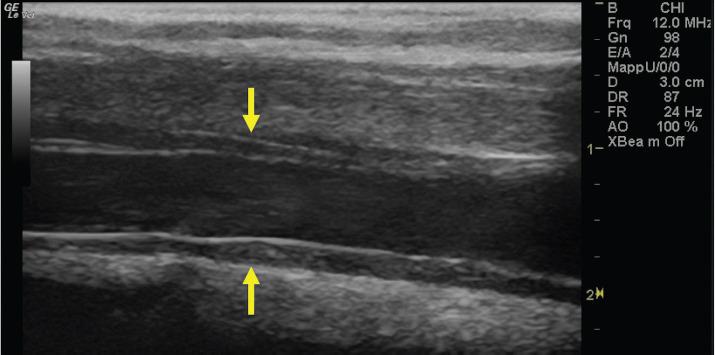

Use of saline contrast ultrasonography in the diagnosis of complete jugular vein occlusion in a horse.

The present report describes a clinical case of equine jugular vein thrombosis (JVT) with complete vein occlusion diagnosed by saline contrast ultrasonography (SCU) and confirmed by contrast venography.

Our results demonstrated that the SCU test can be easily performed and objectively interpreted using standard ultrasound equipment; it is not expensive and it does not require x-ray exposure. The SCU test is a valid tool to assess vessel patency and presence of collateral circulation in JVT. The test could therefore be used to monitor the progression of the disease and the effectiveness of therapy against JVT in horses.